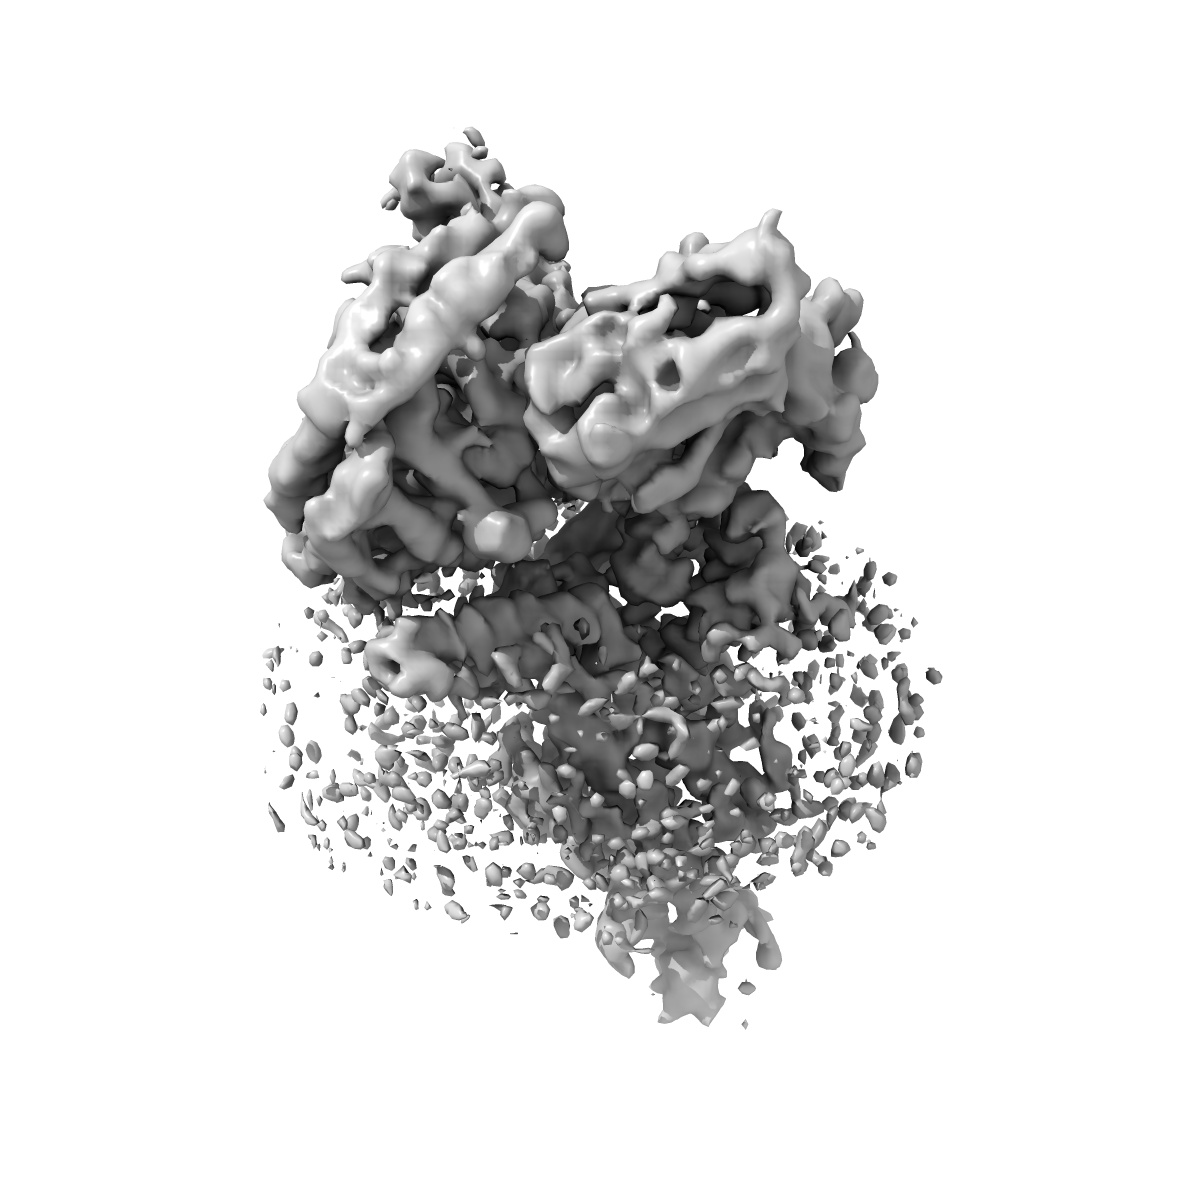

Cryo-EM structure of parathyroid hormone receptor type 1 in complex with a long-acting parathyroid hormone analog and G protein

Single-particle4.0 Å

Sample: Cryo-EM structure of parathyroid hormone receptor type 1 in complex with a long-acting parathyroid hormone analog and G protein

Fitted models: 6nbi